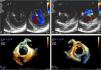

Esta é uma situação bem diferente das fendas observadas em válvulas mitrais estruturalmente normais. Sendo mais comuns no folheto anterior, a solução de continuidade não só não divide o folheto em duas partes distintas, como apresenta uma orientação diferente, direcionada à câmara de saída do ventrículo esquerdo (Figura 2).

A,B – 2D janela transgástrica. Em diástole (A) e em sístole (B) observamos uma fenda do folheto anterior (*) numa válvula mitral.

Fig. 2C,D – 3D zoom em tempo real cropped images. Em diástole, fenda do folheto anterior por vista auricular (C) e ventricular (D). Repare‐se na orientação típica da fenda para o trato de saída do ventrículo esquerdo.